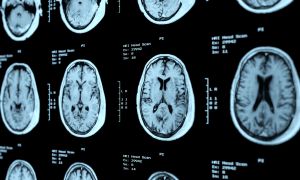

A decreased appetite is not uncommon with a concussion. Nausea is one of the most common concussion symptoms and can be perceived as a lack of appetite. Other concussion symptoms that can contribute to lack of appetite are headache and increased fatigue.